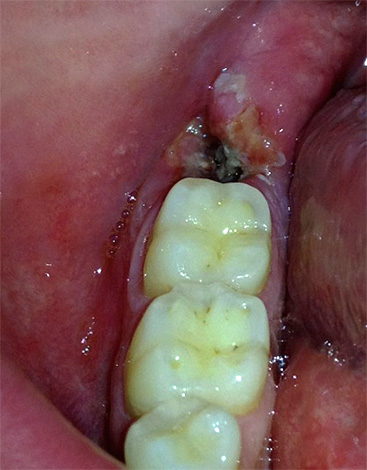

La foto sotto mostra le fasi iniziali della procedura per la rimozione del dente del giudizio retinirovannogo (cioè nascosto sotto la gomma):

- radici fortemente curve (a volte anche ad angolo retto - vedi l'esempio nella foto);